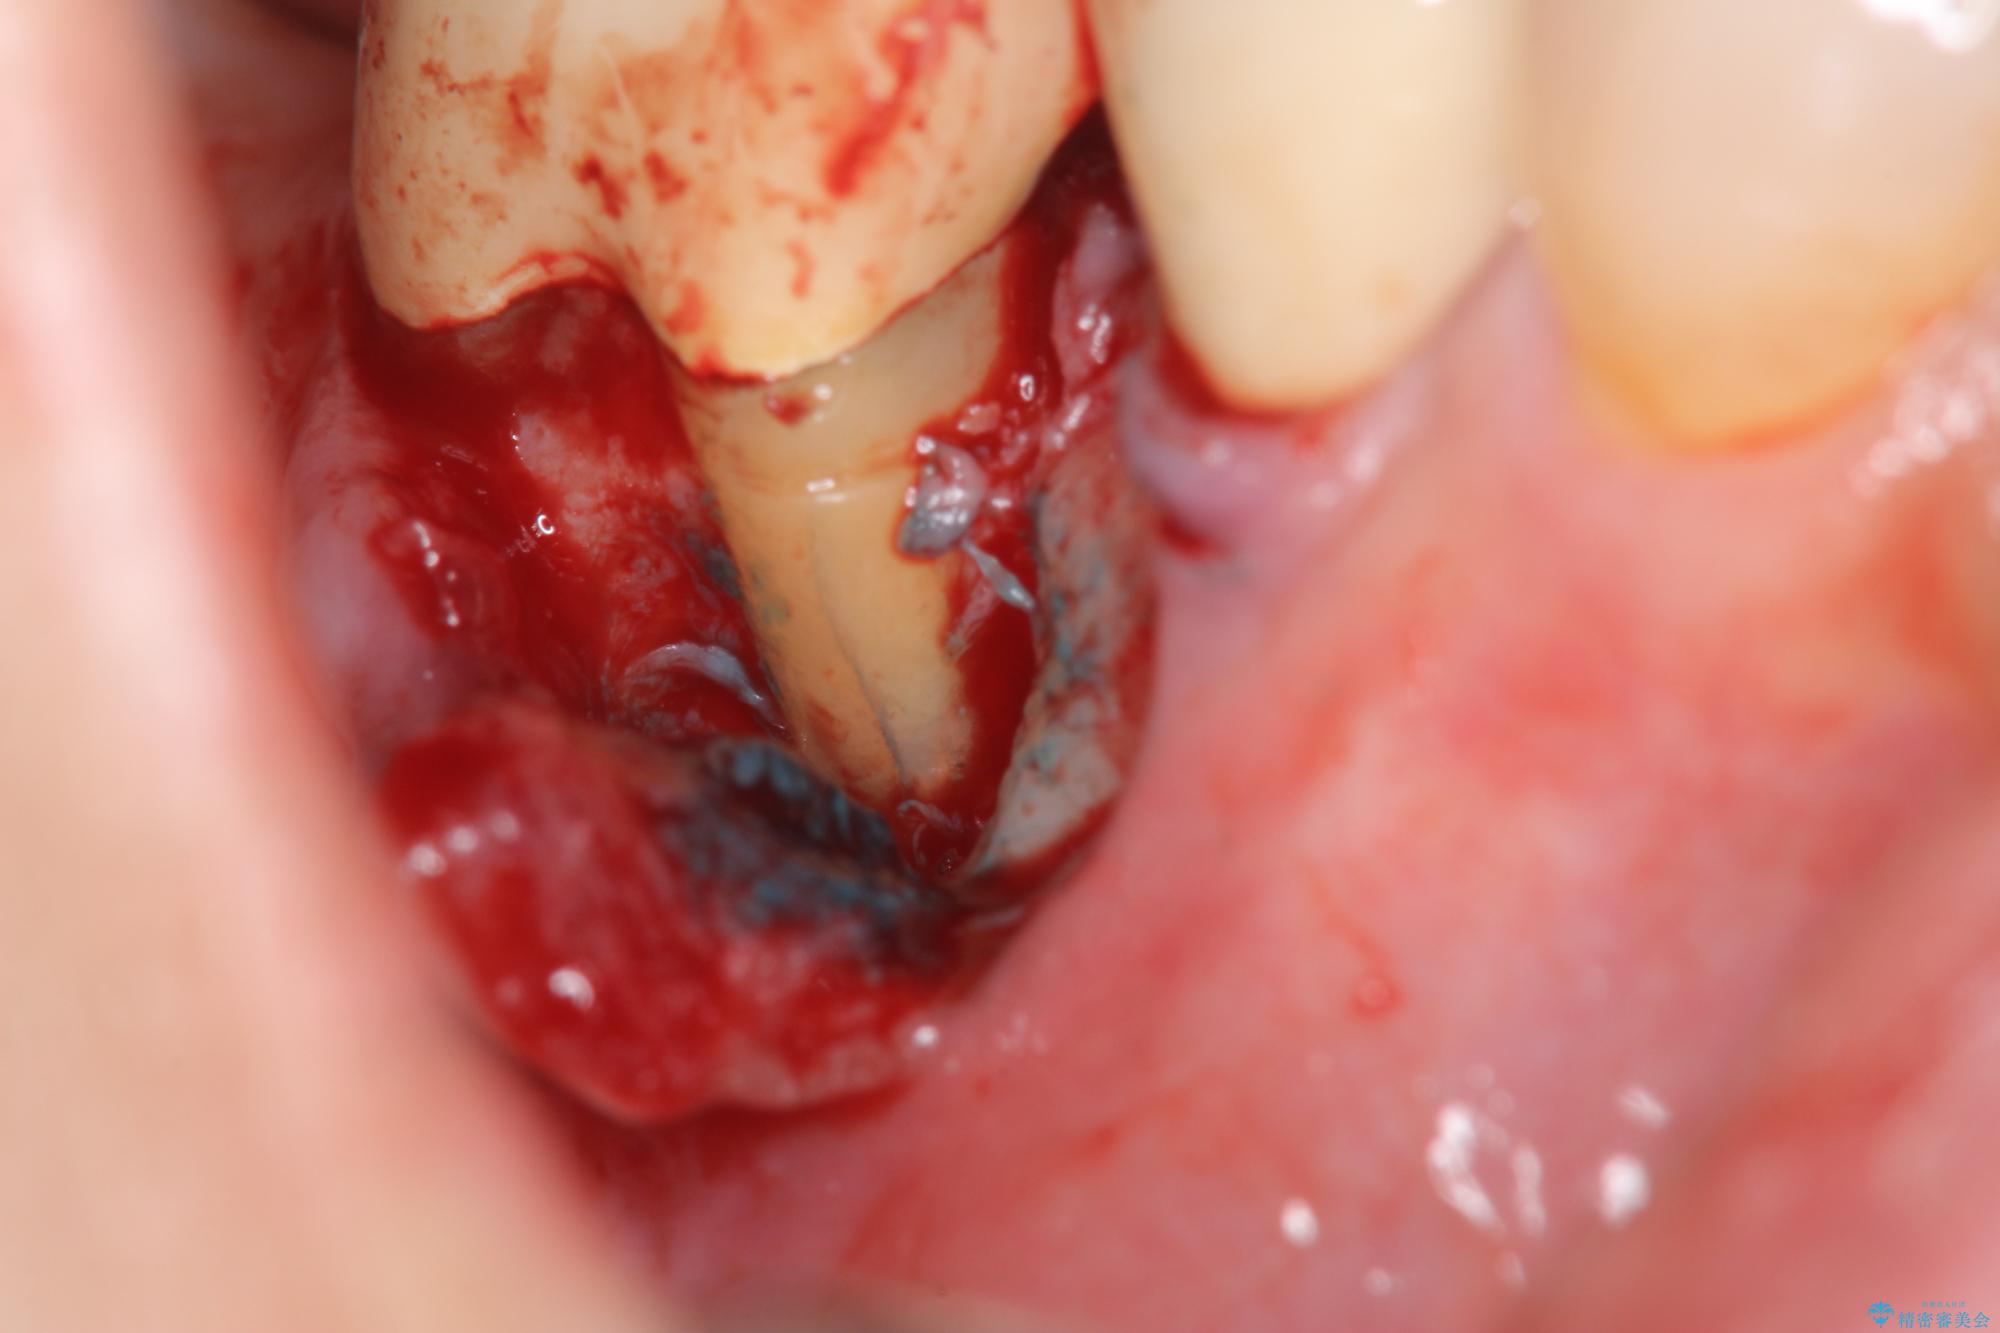

治療中

奥歯から膿のにおいがする インプラントによる機能回復 治療中画像 奥歯から膿のにおいがする インプラントによる機能回復 治療中画像 奥歯から膿のにおいがする インプラントによる機能回復 治療中画像 奥歯から膿のにおいがする インプラントによる機能回復 治療中画像

精査した結果、奥歯の根は破折しており抜歯を避けられない状況でした。

咬合力が強く、その他の歯の破折も防ぐために奥歯の咬合機能をインプラントを用いて回復する治療計画を立てます。